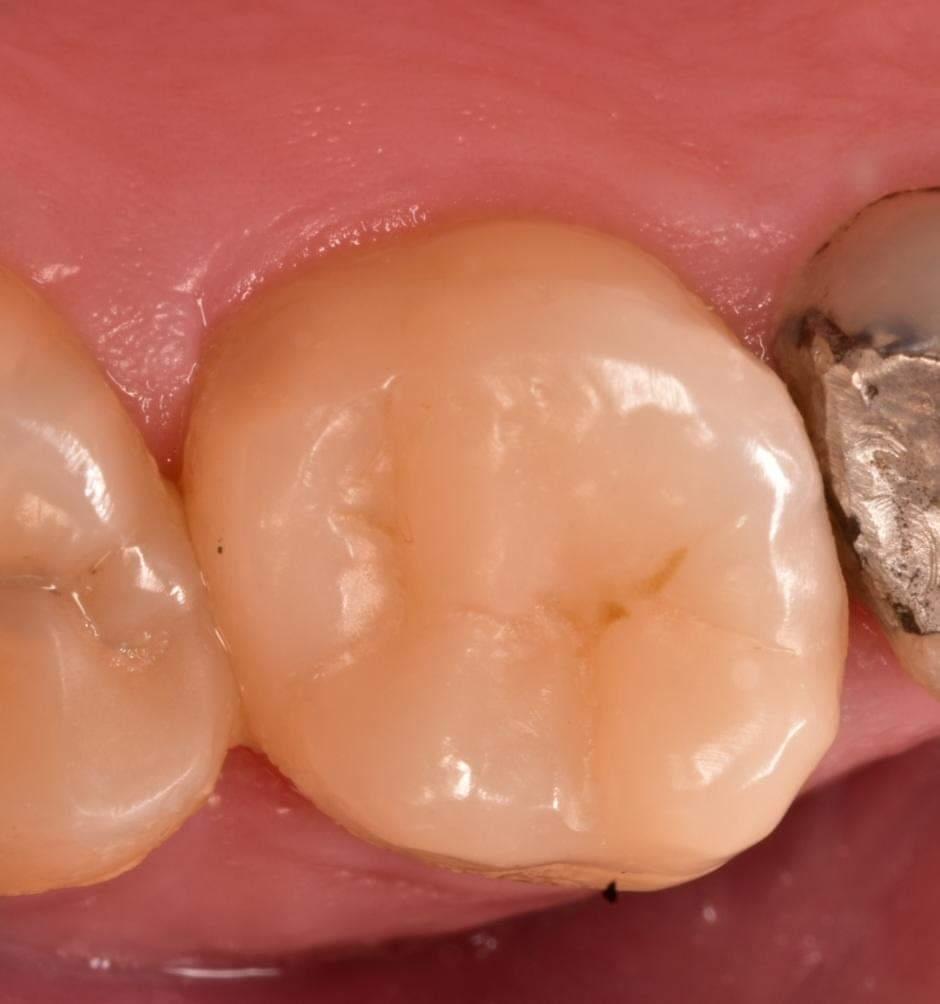

After rubber dam removal

Final result,